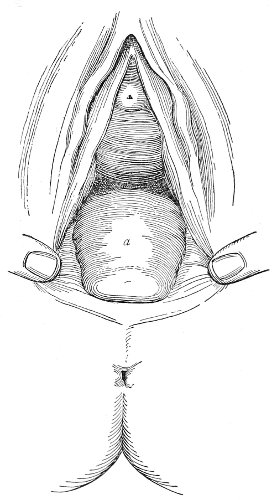

Slight Median laceration of the Perineum.—In this injury the tear takes place through the fourchette. Posteriorly it may extend as far as the sphincter ani muscle. Upward it may extend for an inch up the posterior vaginal wall. The appearance of this tear is shown in Fig. 33. It will be noted that, as this tear takes place in the median line, none of the muscles that support the perineum are involved, nor are the planes of fascia injured. The perineum is slightly split, and the insertions and origins of the muscles and the fascia are slightly separated. The supporting structures of the perineum and the pelvic floor are, however, uninjured.

Fig. 33.—Recent slight median laceration of the perineum: sutures introduced.

If this tear is detected after labor, it should be closed by the immediate operation. A slight tear involving chiefly the cutaneous aspect of the perineum should be closed by three or four sutures introduced from the outside, as in Fig. 33. The needle should be introduced about a quarter of an inch from the edge of the wound. It should not be passed parallel with the plane of the lacerated surface, but should be swept outward and then inward toward the 68 angle at the bottom of the tear (Fig. 34). It may either emerge at the angle and be re-introduced, or it may be passed directly through to the skin-margin on the opposite side of the wound. If the suture is passed in this way, there will be perfect apposition throughout the whole surface of laceration. If the sutures are improperly passed, there may result only apposition of the skin-edges.

Fig. 34.—Diagram representing the correct and the incorrect method of passing the suture for closure of slight perineal laceration.

If the laceration extends up the posterior vaginal wall, two sets of sutures must be introduced—one on the vaginal aspect of the tear, and one on the skin aspect (Fig. 35).